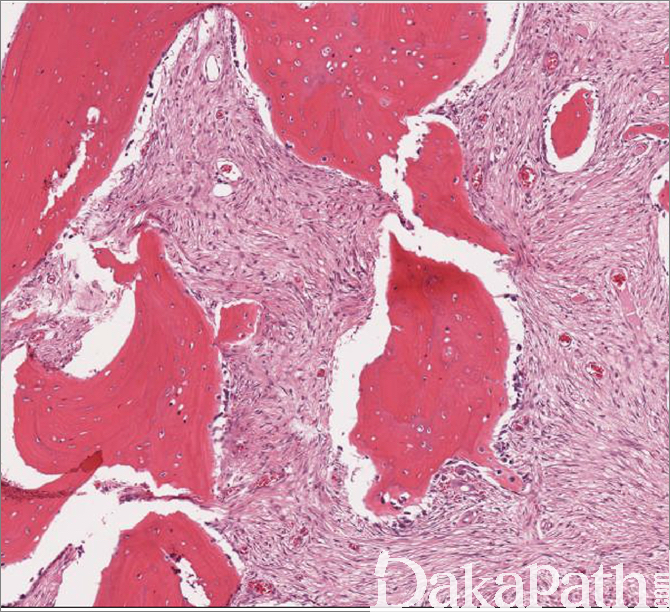

镜下由纤维样组织及骨小梁组成,纤维样组织中密度中等的梭形细胞呈席纹状排列,梭形细胞较温和,核呈锥形及不易辨认的嗜酸性胞浆,核分裂活性较低。

间质可呈水肿样及纤维黏液样改变,可见大量毛细血管。

编织骨小梁排列紊乱,不规则、曲线状排列,少数可见黏合线。编织骨之间无连续性,好像直接来自纤维组织,周围无明显的骨母细胞围绕,可出现大量的破骨细胞,胶原纤维可直接从纤维间质延伸至编织骨。